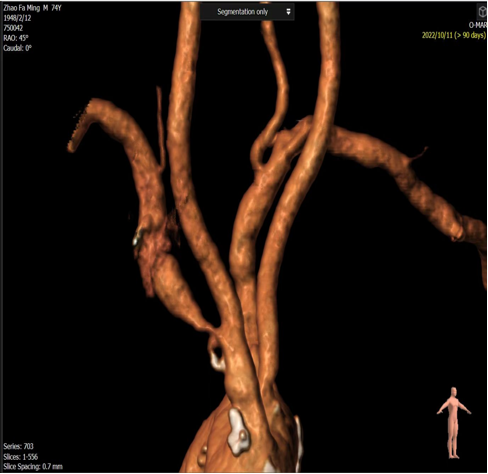

右锁骨下动脉与颈动脉开口狭窄(对吻支架技术):

对于头臂干分叉处病变,需要同时对右锁骨下动脉和颈动脉植入支架(对吻支架)。术前CTA重建确定了最佳角度,术中直接采用该角度进行造影和支架释放,确保了双支架的精准定位,避免相互影响。

图:CTA图像

图:术中CTA图像指导导丝导管方向